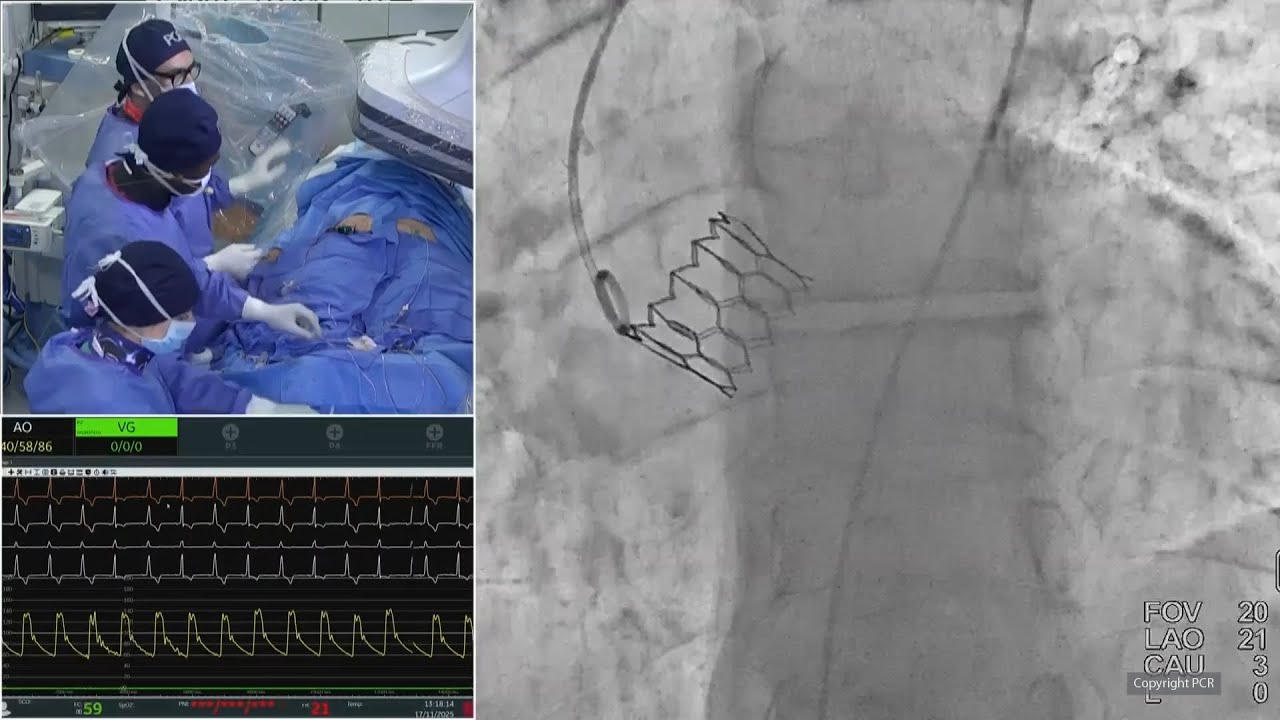

TAVI for bioprosthetic valve failure: LIVE Educational Case from Institut Cardiovasculaire Paris Sud - Massy, France